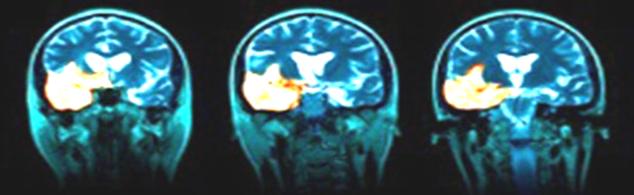

Hình ảnh học

Thực hiện đầu tiên khi nghi ngờ viêm não.

Cung cấp thông tin đánh giá nhiễm trùng hệ thần kinh TW nhưng thường không đặc hiệu. Phát hiện sau khởi phát triệu chứng 2-4 ngày.

MRI nhạy hơn CT trong việc phát hiện sớm những sang thương trên não do HSE (Neurologist 2000;6:145–59.)

Tổn thương gợi ý chẩn đoán: T1 giảm và T2 tăng ở chất xám thuỳ thái dương trong và thuỳ trán ổ mắt, có thể có xuất huyết kèm theo, thường không đối xứng. Ngoài ra tổn thương có thể lan đến thuỳ đảo và hồi góc, có thể bắt Gado màng não và các hồi não.

MRI bình thường trong khoảng 10% BN HSV-PCR (+). Nhưng số còn lại đều có tổn thương thuỳ thái dương (90%)